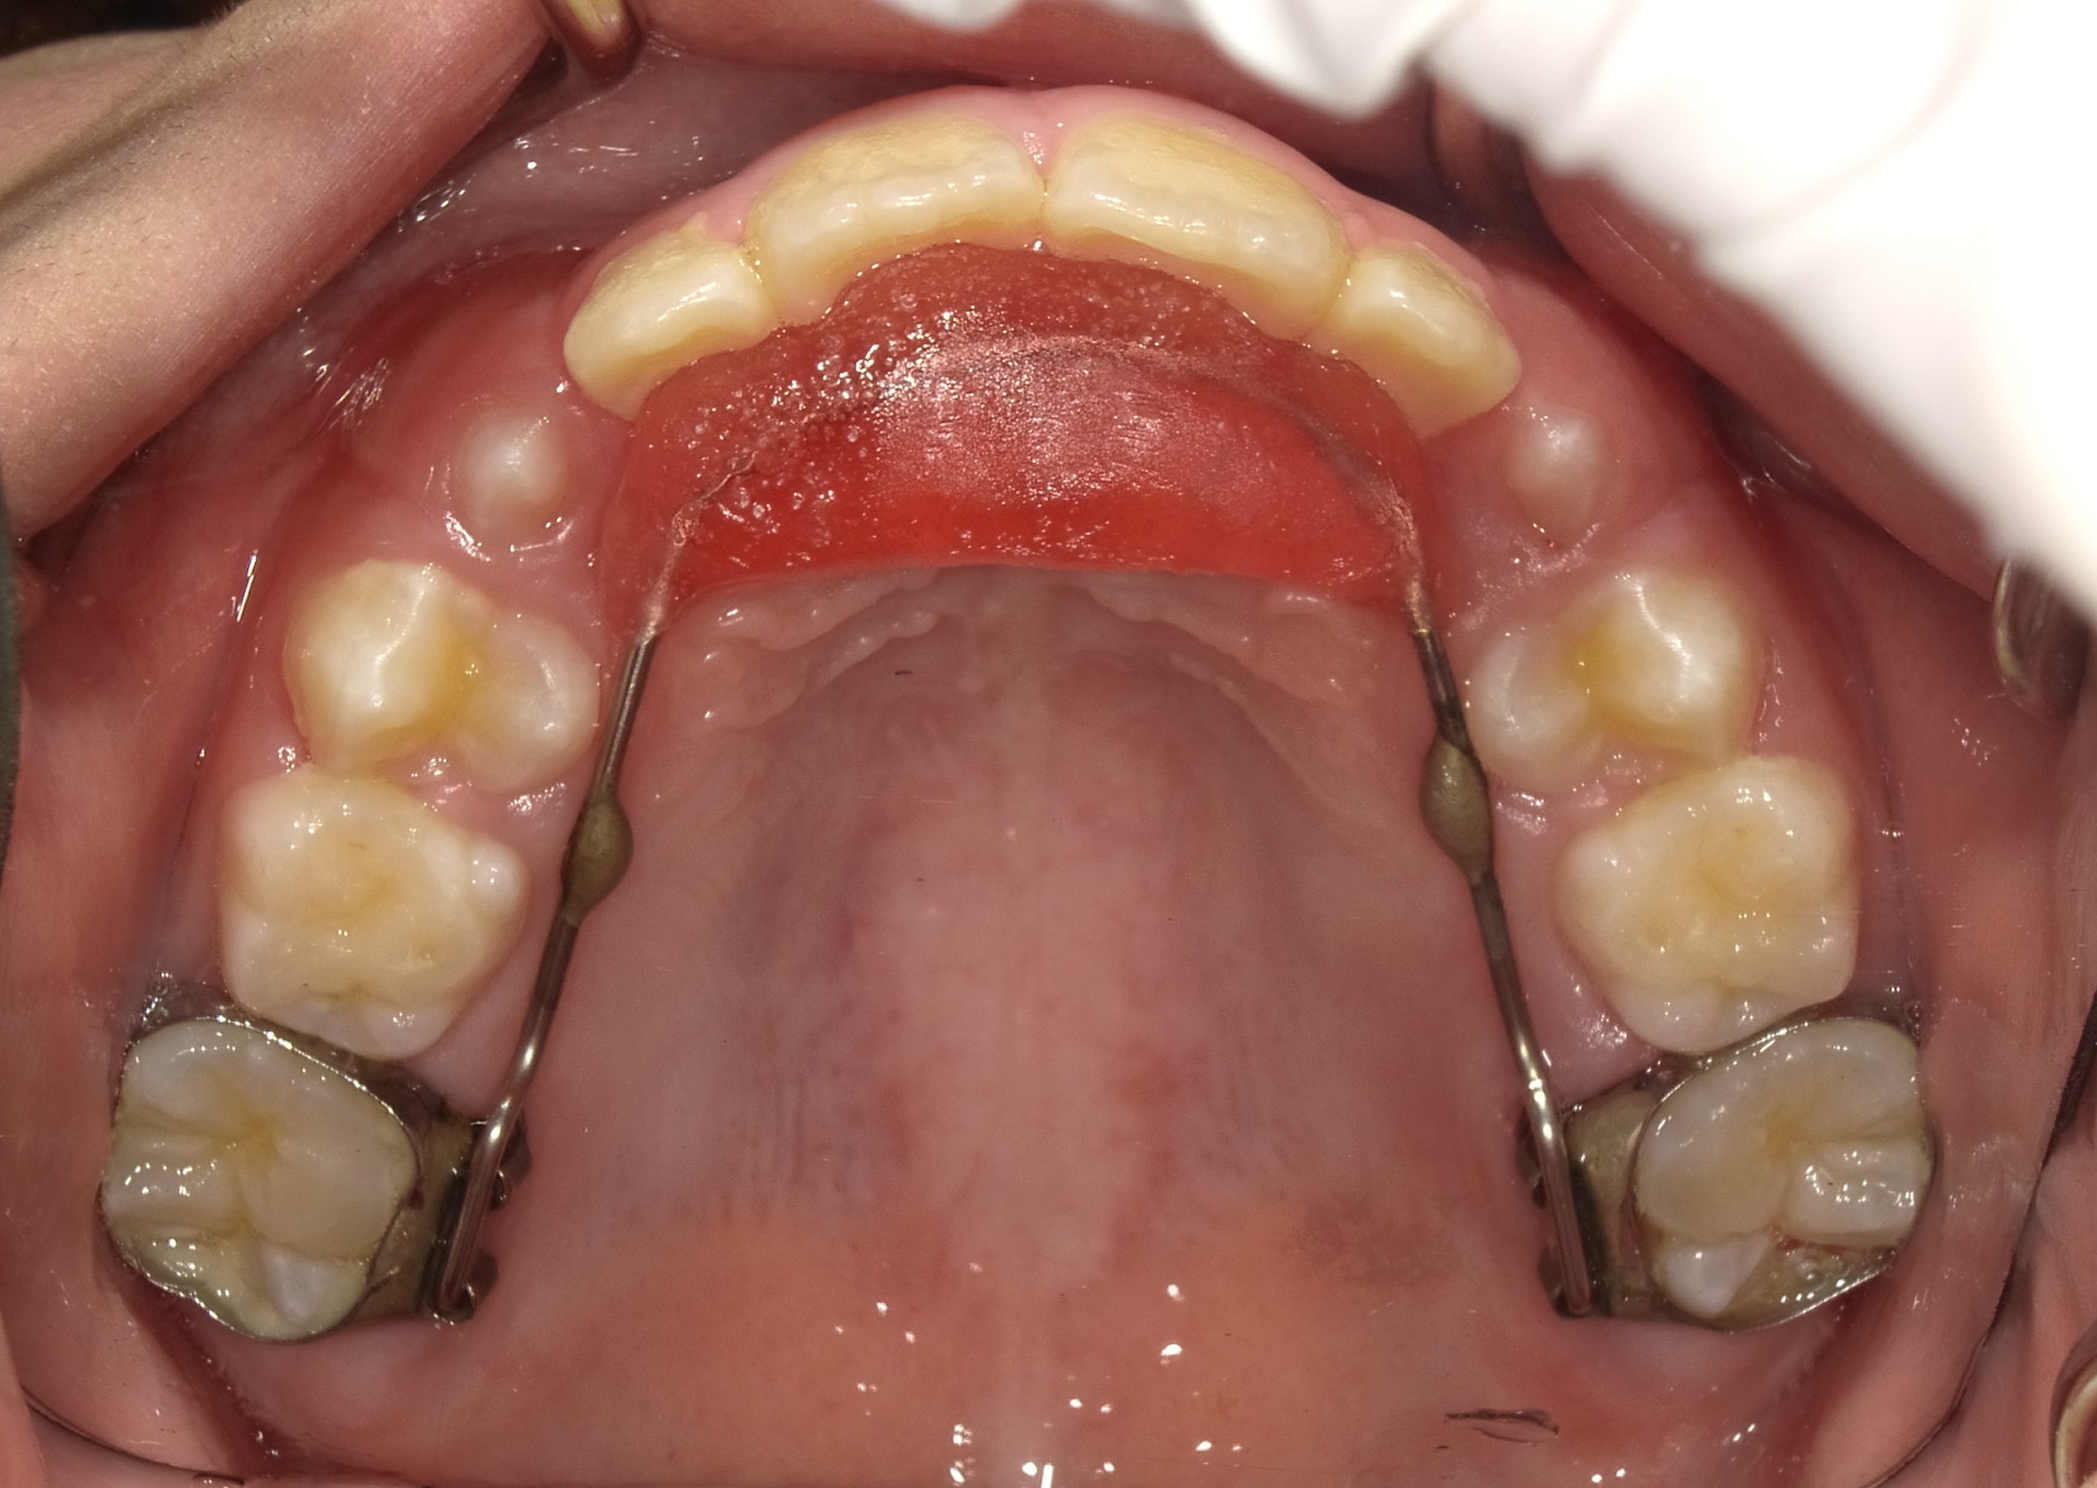

1期矯正

まずは拡大床という装置を使い、凸凹の改善を目指します。

装置使用前後の比較

前歯に若干の凸凹はありますが、あとは2期治療で簡単に改善可能です。